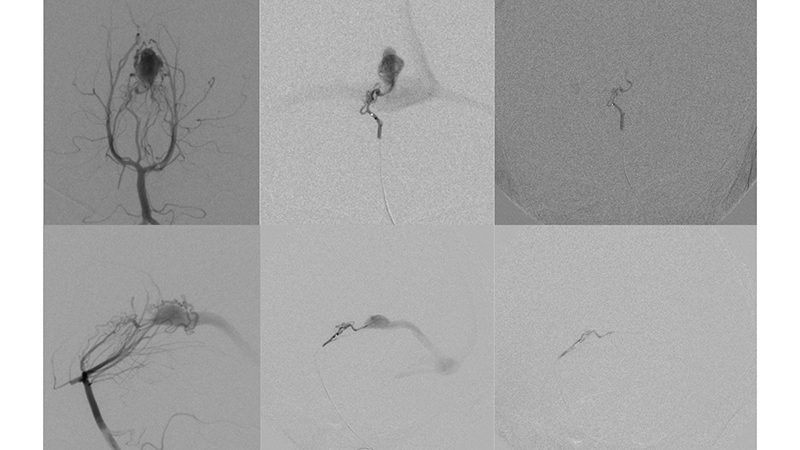

- Καθετηριασμός και εμβολισμός με κυανοακρυλική κόλλα θαλαμοδιατιτραινόντων κλάδων.

- Καθετηριασμός και εμβολισμός με κυανοακρυλική κόλλα υποεπενδυματικών κλάδων.

- Καθετηριασμός και εμβολισμός με κυανοακρυλική κόλλα οπισθιοπλαγίων χοριοειδών κλάδων.

Ως αποτέλεσμα της ανωτέρω αιμοδυναμικής μεταβολής και με δεδομένη την ιακνοποιητική κλινική βελτίωση, αποφασίσθηκε να μην γίνει επέμβαση και ο ασθενής να τεθεί υπό χαμηλού μοριακού βάρους ηπαρίνη λόγω της θρομβώσεως των οπισθίων φλεβωδών κόλπων. - Δύο χρόνια αργότερα, υπερεκλεκτικός καθετηριασμός υποεπενδυματικών και χοριοειδών τροφοφόρων κλάδων από το Ρ1, Ρ2 και Ρ3 των οπισθίων εγκεφαλικών αρτηριών.

- Υπερεκλεκτικός καθετηριασμός υποεπενδυματικών και χοριοειδών τροφοφόρων κλάδων από το Ρ1, Ρ2 και Ρ3 των οπισθίων εγκεφαλικών αρτηριών.

- Τελική αγγειογραφία επανελέγχου του σπονδυλοβασικού μετά την δεύτερη συνεδρία εμβολισμού. Παραμένουν δύο με τρεις μικροί τροφοφόροι αρτηριακοί θαλαμοδιατιτραίνοντες κλάδοι από το Ρ1 τμήμα της αριστερής οπίσθιας εγκεφαλικής αρτηρίας, που λόγω του πολύ μικρού νεγέθους των θα αντιμετωπισθούν μετά από 2 έτη. Η φλεβική παροχέτευση γίνεται προς την φλέβα του Γαληνού, και διά μέσου επιπολής φλεβός προς την έσω επιφάνεια του αριστερού βρεγματικού λοβού προς τον άνω οβελιαίο κόλπο. Οι εγκάρσιοι κόλποι και ο Ληνός έχουν επανασηραγγοποιηθεί.

- Παρατηρείται πλήρης αποσυμφόρηση του περιμεσεγκεφαλικού φλεβικού δικτύου με σημαντική ελάττωση της φλεβικής συμφορήσεως περιμεσεγκεφαλικά καθώς και προς τον νωτιαίο μυελό.